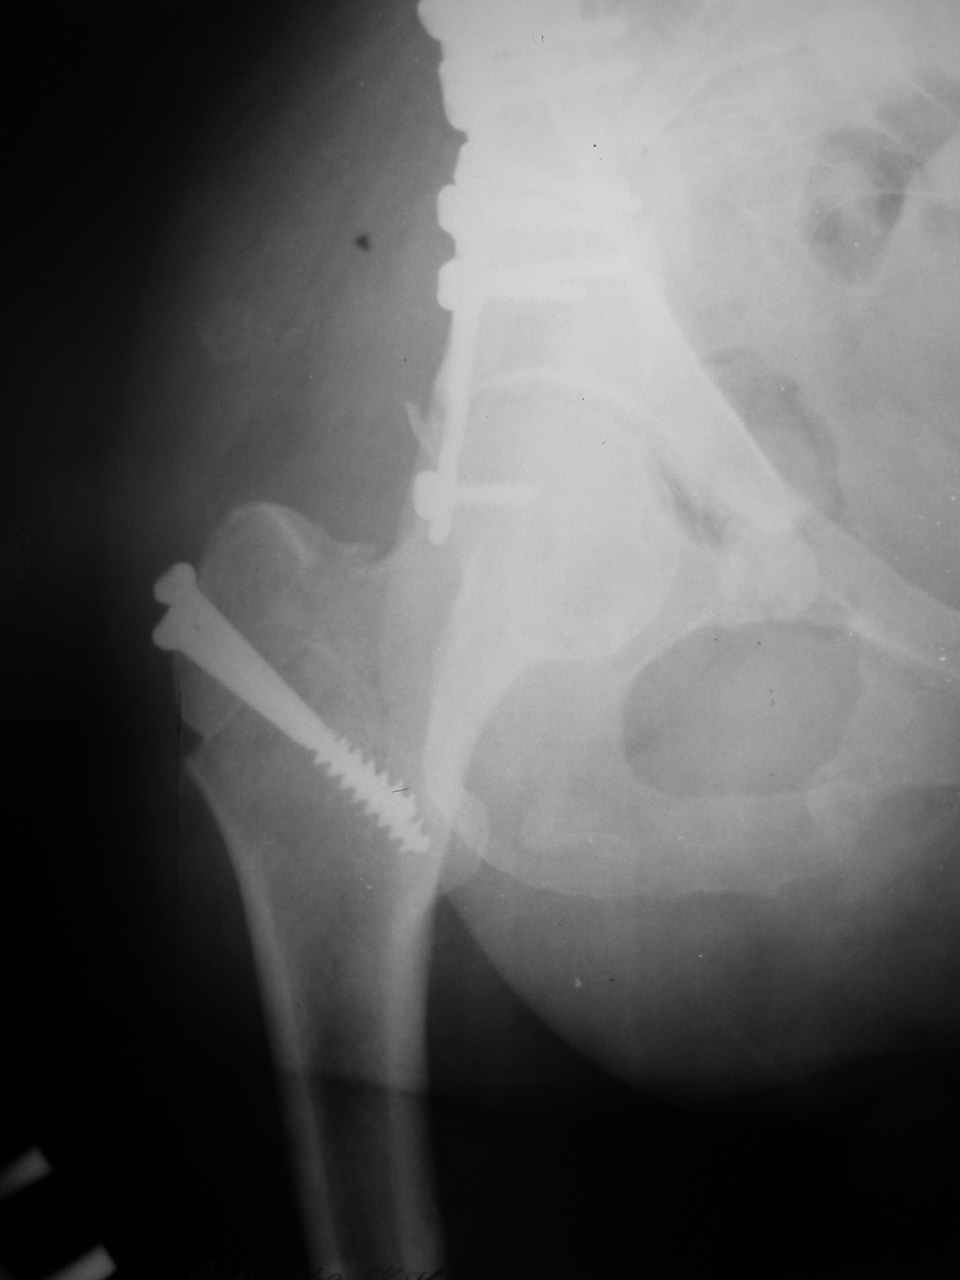

Спасибо за комментарии и рекомендации. Откровенно говоря, больного я прооперировал на прошлой неделе, через 5 дней после аварии и проблем с ним пока никаких нет, на удивление при достаточно обширной диссекции (илиофеморальный доступ) болей практически нет, так что больной самостоятельно садится в кровати, выполняет активные движения в оперированном суставе, сгибая до 60 градусов пока, далее с ассистенцией.

Причиной обращения к сообществу были возникшие непосредственно после операции сомнения и разочарования полученным качеством репозиции: а надо ли было трогать перелом вообще, репозиция передней колонны технически была очень сложна для меня, хотя реконструкции была в той же последовательности, что Д-р А.В.Рунков рекомендовал, в какой-то момент безуспешных манипуляций стал думать о *вторичной конгруэнтности*, которую не так давно обсуждали на

форуме и скелетном вытяжении. С репозицией и фиксацией задней колонны и отдельно задне-верхней стенки впадины проблем не возникло. Послеоп. Рг граммы в приложении. Если возникнут какие-либо дополнения или поправки - был бы признателен.